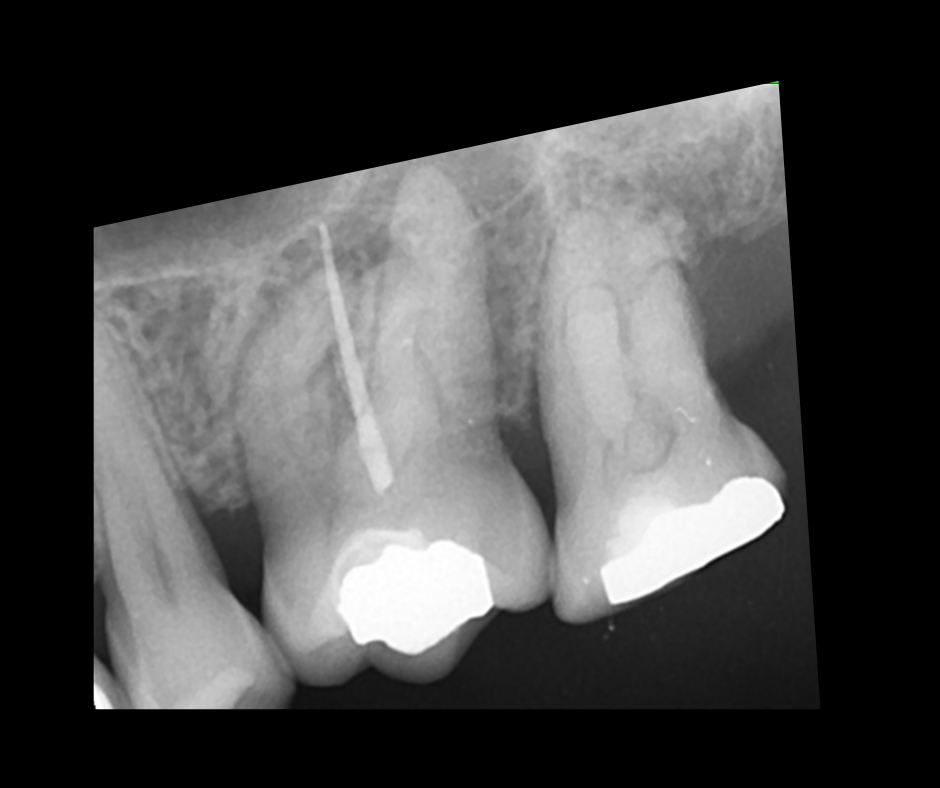

• To understand the importance of achieving patency and mechanical glidepath with hand & NiTi instruments

• To gain confidence in mechanical preparation using rotary and reciprocating NiTi shaping instruments

• To acknowledge the updates in endodontic irrigation and methods of improving irrigation efficacy within the root canal system

11.45 – 13.00 – Contemporary NiTi 1: Canal Location, Scouting, Patency and Glidepath

14.00 – 16.00 – Contemporary NiTi 2: Mechanical Preparation and Update on Irrigation